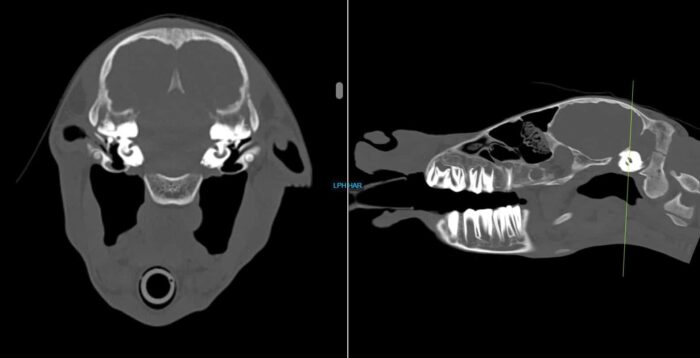

Nova, an 8-day old Quarter Horse filly, presented to Animal Imaging following a 2-day history of right sided head tilt with no known evidence of trauma. She was worked up by a boarded internal medicine specialist who found no significant abnormalities on physical examination, bloodwork, and initial radiographic findings.